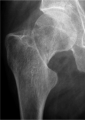

A new measurement for posterior tilt predicts reoperation in undisplaced femoral neck fractures: 113 consecutive patients treated by internal fixation and followed for 1 year. Palm H, Gosvig K, Krasheninnikoff M, Jacobsen S, Gebuhr P - Acta orthopaedica (2009)

| current | 18:24, 13 May 2021 | 244 × 344 (67 KB) | Rossdonaldson1 (talk | contribs) | A new measurement for posterior tilt predicts reoperation in undisplaced femoral neck fractures: 113 consecutive patients treated by internal fixation and followed for 1 year. Palm H, Gosvig K, Krasheninnikoff M, Jacobsen S, Gebuhr P - Acta orthopaedic... |